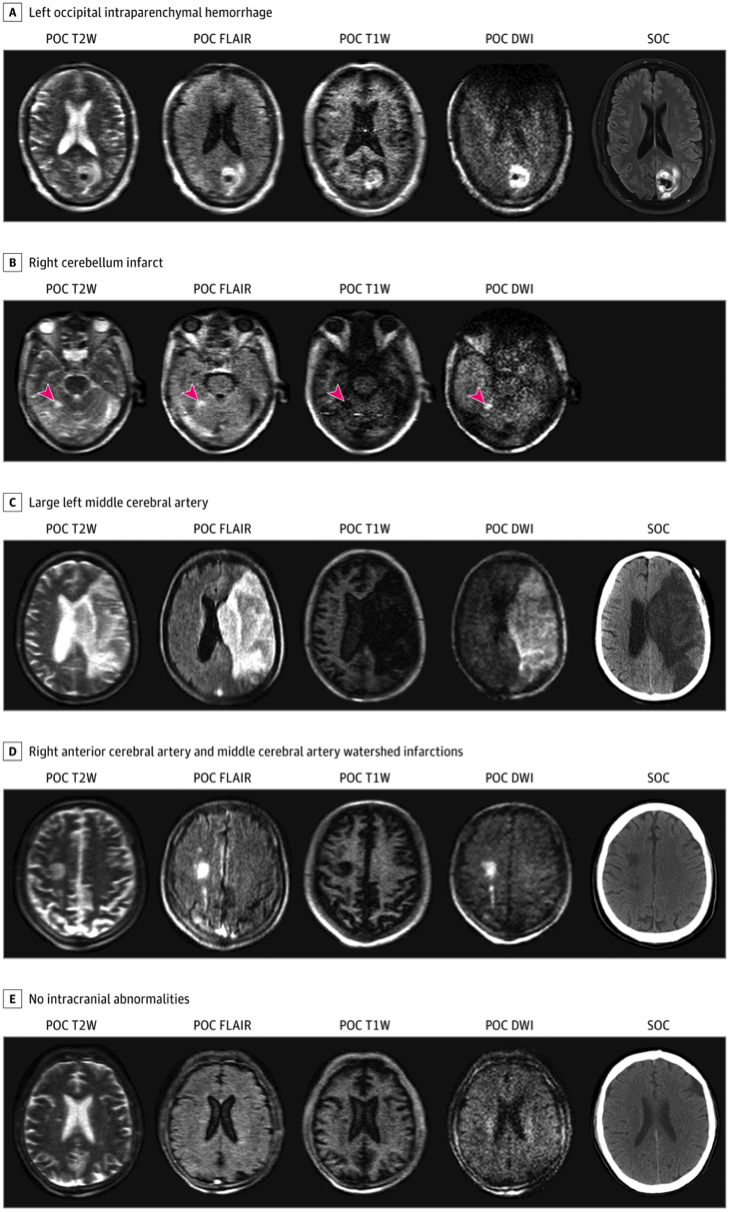

Различные виды патологий на портативной МРТ (POC) по сравнению со стационарными МРТ и КТ. Credit: Kevin N. Sheth et al.

Тем не менее оборудование нуждалось в клинической проверке, которую провели исследователи из Йельского университета. Они испытали его на 50 реанимационных пациентах с с ишемическим и геморрагическим инсультами, субарахноидальным кровоизлиянием (когда кровь изливается под вторую оболочку мозга – арахноидальную), черепно-мозговой травмой, опухолями головного мозга и измененным психическим статусом при COVID-19. Проводились сканирования в среднем через пять дней после поступления в отделения интенсивной терапии (диапазон 0–37 дней). При этом почти треть пациентов находилась под наркозом, а еще трети проводилась искусственной вентиляции легких. Пациентам также проводили обычное МРТ- и КТ-сканирование.

В целом, исследования почти всех пациентов по качеству и диагностической информативности были сопоставимы со стандартными. Поскольку свежая кровь имеет такие физические характеристики, что не визуализируется на МРТ, субарахноидальное кровоизлияние выявить не удалось. Не визуализировались и какие-либо органические поражения при COVID-19 (которых на самом деле не было).